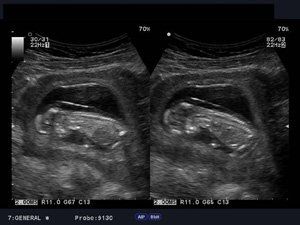

Sonogram Image Of 12 Week Old Fetus High-Res Stock Photo - Getty Images

Source: gettyimages.com

week fetus old sonogram human embryo only istock royalty res high premium gettyimages.

What Is Your Diagnosis: Fetus At 12 Weeks Gestation

Source: contemporaryobgyn.net

fetus.